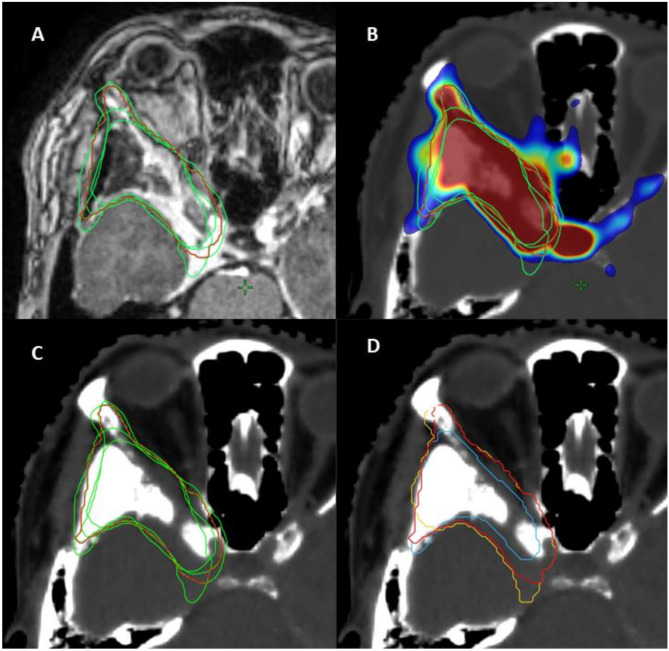

Background: Precise delineation of gross tumor volume (GTV) is fundamental for effective radiation therapy in low-grade skull base meningiomas. Magnetic resonance imaging (MRI) serves as the primary imaging tool but may not fully represent tumor extent. This study investigates the additional value of incorporating Somatostatin receptor (SSTR)-directed PET/CT in radiation therapy planning.

Methods: A retrospective analysis was conducted with four experienced radiation oncologists contouring GTVs for skull base meningiomas using MRI alone (GTV_MRI), PET/CT alone (GTV_PET/CT), and both modalities combined (GTV_ALL). Consensus ground truth volumes were generated for each modality through a STAPLE algorithm. Agreement between modalities, excluding observer variability, was assessed using statistical metrics including Dice Similarity Coefficient (DSC), Jaccard Index (JCI), Hausdorff distance (HD95), Geographical Miss Index (GMI), sensitivity, and kappa statistics.

Results: The study included 25 patients (15 females, 10 males; median age 56 years (range: 23-74 years), with 96% achieving local control post-radiotherapy over a median follow-up of 64 months (range: 28-135 months). Substantial interobserver agreement was observed, with median kappa values of 0.74 for GTV_MRI, 0.68 for GTV_PET/CT, and 0.77 for GTV_ALL. Median consensus volumes were 6.65 cc (MRISTAPLE), 7.21 cc (PETSTAPLE), and 6.73 cc (ALLSTAPLE). The median GMI for MRISTAPLE compared to ALLSTAPLE was 0.18 (IQR: 0.11-0.39), and 0.21 (IQR: 0.15-0.28) for PETSTAPLE compared to ALLSTAPLE. The DSC indicated the lowest concordance between MRISTAPLE and PETSTAPLE with a median of 0.75 (IQR: 0.59-0.82), followed by PETSTAPLE versus ALLSTAPLE with a median DSC of 0.84 (IQR: 0.79-0.89), and MRISTAPLE versus ALLSTAPLE with a median DSC of 0.89 (IQR: 0.76-0.92). The integration of PET/CT with MRI significantly enhanced concordance metrics.

Conclusion: Combining MRI and PET/CT improves GTV delineation in low-grade skull base meningiomas, as PET/CT can reveal regions missed by MRI, which may slightly underestimate tumor size. This multimodal imaging approach enhances consensus and supports its role in radiotherapy planning. Standardized protocols and technical integration remain key future goals.